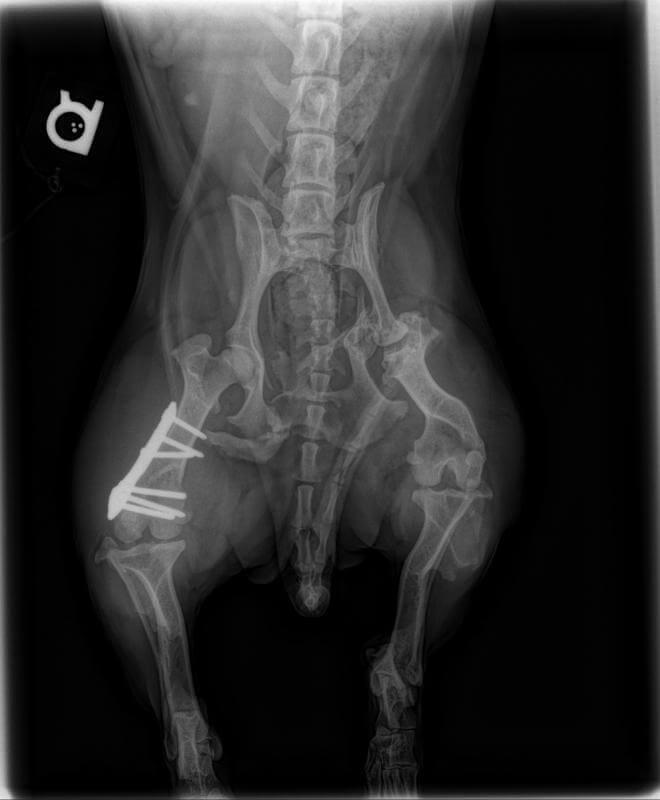

X-ray of dog's pelvis with bone plate in right hip

Our practice uses digital radiology both for dental purposes and for your pet’s whole body. Dental digital radiology allows our practice to view the internal anatomy of the teeth including the roots and surrounding bone. In the rest of your pet’s body, digital x-rays can help us identify a fractured bone, or degeneration in a joint as well as sometimes identify foreign objects inside your pet’s body. An added bonus to digital radiology is the fact that it emits less radiation than traditional radiology.